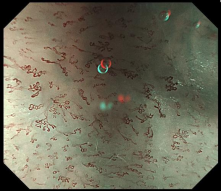

图示:放大胃镜下早期胃癌的微结构排列紊乱,微血管呈现扭曲、形态不规则